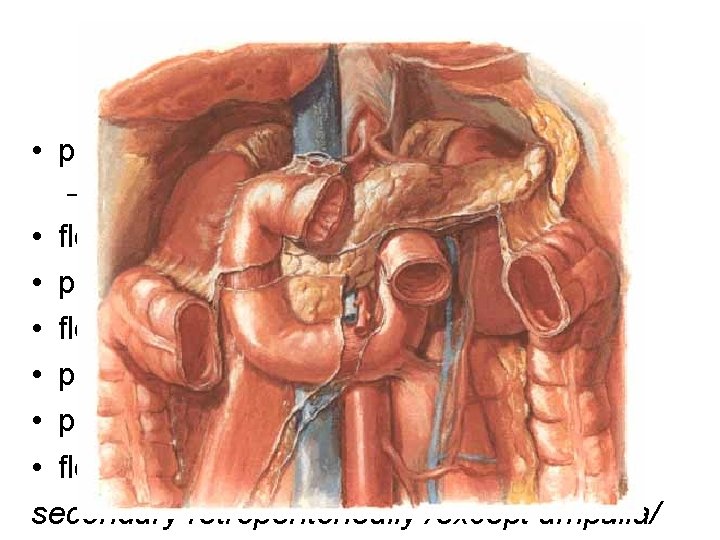

Unpaired branches of the aorta abdominalis

Stomach – arterial supply truncus coelicacus • aa. gastrica sin. • a. hepatica communis – a. hepatica propria a. gastrica dx. – a. gastroduodenalis a. gastroomentalis dx. • a. splenica a. gastroomentalis sin. , aa. gastricae breves (fundus), a. gastrica posterior (variability)

Duodenum – blood supply • truncus coelicacus a. hepatica communis a. gastroduodenalis a. pancreaticoduodenalis sup. post. + sup. ant. + aa. retroduodenales • a. mesenterica sup. a. pancreaticoduodenalis inf. ramus ant. + r. post. Veins: vv. pancreaticoduodenales v. mesenterica sup. v. portae